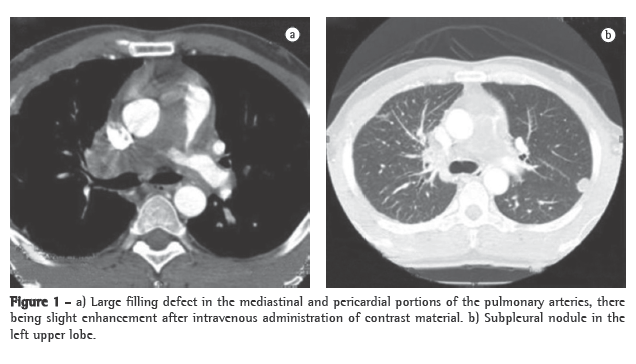

A transthoracic Doppler echocardiogram, which had been performed previously, showed moderate right heart enlargement, and pulmonary artery systolic pressure (PASP) was estimated to be 76 mmHg. A transesophageal echocardiogram demonstrated extensive thrombosis in the pulmonary artery trunk and PASP of 57 mmHg. Ultrasonography of the lower limbs revealed no signs of deep venous thrombosis. Lung perfusion scintigraphy, which was performed during hospitalization, showed low uptake in the view of the anterior and the apical-posterior segments of the left lung. The right lung was not visualized. Angiotomography of the chest revealed a large filling defect in the mediastinal and pericardial portion of the pulmonary trunk and arteries, there being enhancement of that defect after intravenous administration of contrast material (Figure 1a). In addition, there were predominantly peripheral nodules on the left (Figure 1b), as well as thickening of interlobular and peribronchovascular septa on the right, associated with upper lobe consolidation, moderate pericardial effusion and a mosaic attenuation pattern (Figure 2).